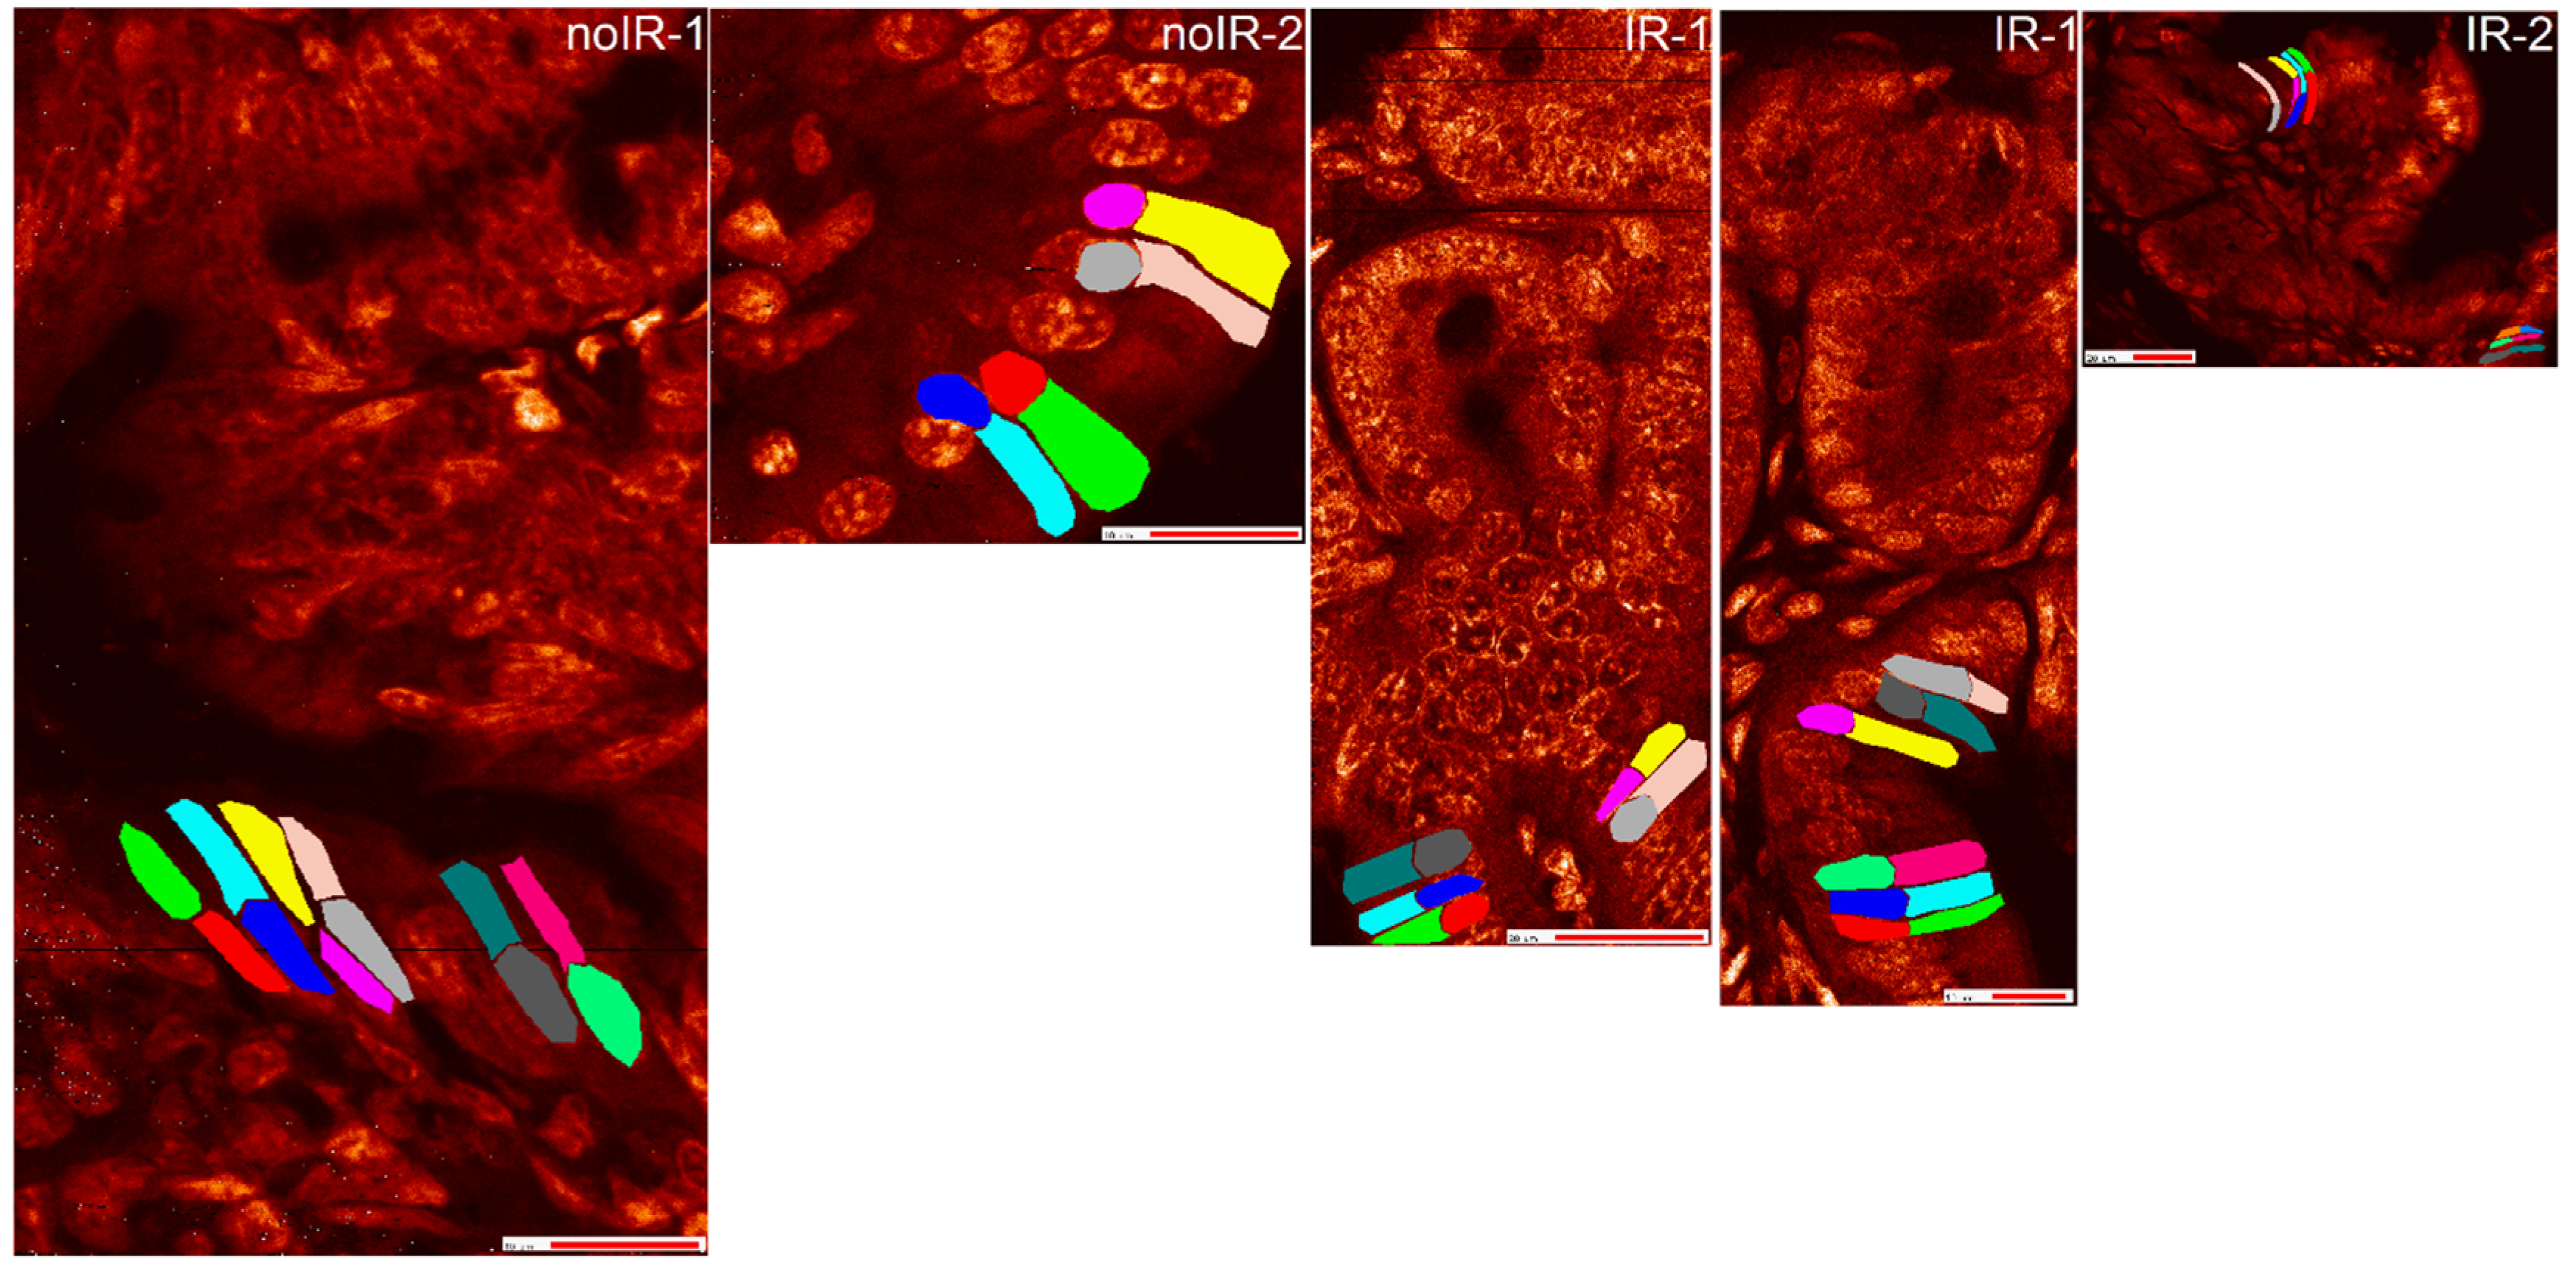

2.2.2. Mean Pixel Concentration Analysis—Individual Cell Analyses

2.2.3. ANOVA Evaluation of Cell-to-Cell Elemental Differences

2.2.4. T-Test Evaluation of Differences between Different Scans of the Same Cells

2.2.5. Tissue Region Analyses